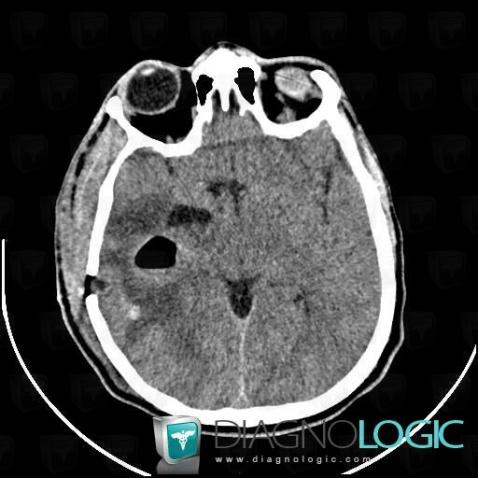

Abscess, Cerebral hemispheres, CT

Here is the specific information in the key image above:

- Diagnosis Abscess, Location(s) Cerebral hemispheres, with gamuts Intracerebral mass, Multifocal intracranial lesions, Intracerebral lesion with moderate enhancement